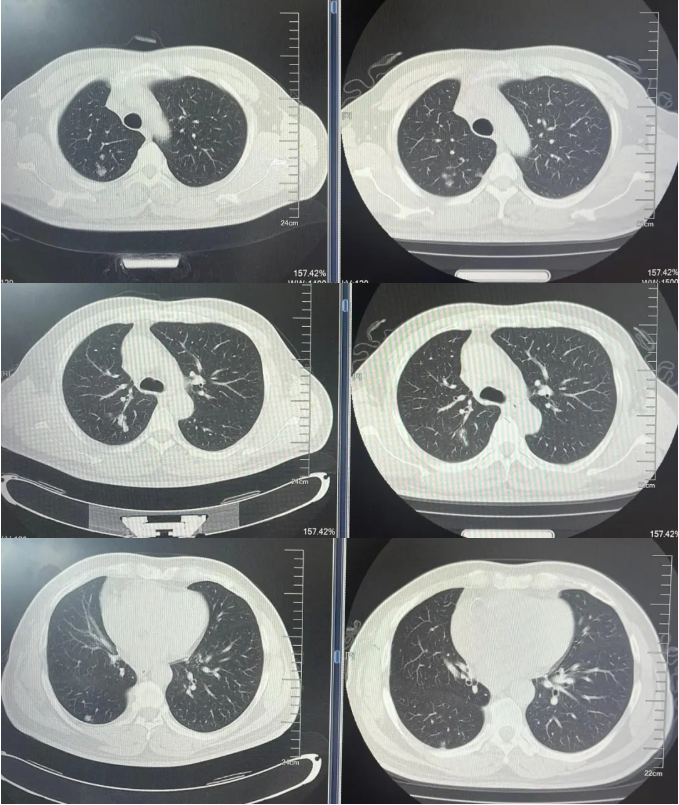

病例2:患者男,61岁。2023年8月于外院行肺CT提示:右肺下叶肿块。2023年10月23日于我院行单孔胸腔镜下右肺下叶切除术、肺门纵隔淋巴结扩清术。术后病理:腺癌低分化(腺泡型占30%,乳头型占30%,筛状占30%,微乳头占10%)。分期pT4N0M0 IIIA期。术后行基因检测提示HER2+(14%),PD-L1 2%+。术后行AC方案化疗4周期后行阿替利珠单抗维持治疗1年。末次用药时间:2024年11月1日。2025年2月复查肿瘤标志物升高,肺HRCT示:双肺多发结节,考虑转移。行血液基因检测提示:ERBB2 35.5%突变,CDK1 9.5%突变,MDM2 4.92%突变。患者DFS 14m,阿替利珠单抗停药后3个月出现复发转移,可见传统免疫治疗效果不佳。恰逢德曲妥珠单抗一线新尝试DESTINY-lung 04研究公布了入组标准和治疗方案,且该患在术后的组织基因检测和复发后的血液基因检测中都明确存在HER2突变,故行德曲妥珠单抗一线治疗。最佳疗效PR,目前治疗持续有效,PFS超过6个月。无药物相关不良反应发生。

德曲妥珠单抗治疗4周期(2025.4)疗效对比